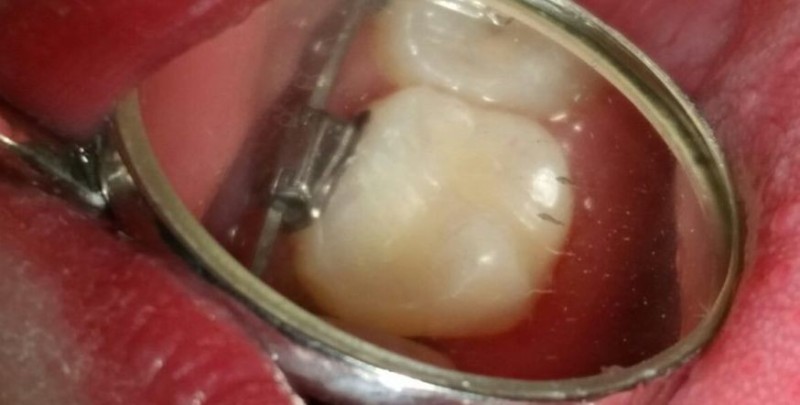

Писарская Елена Николаевна: портфолио (2)